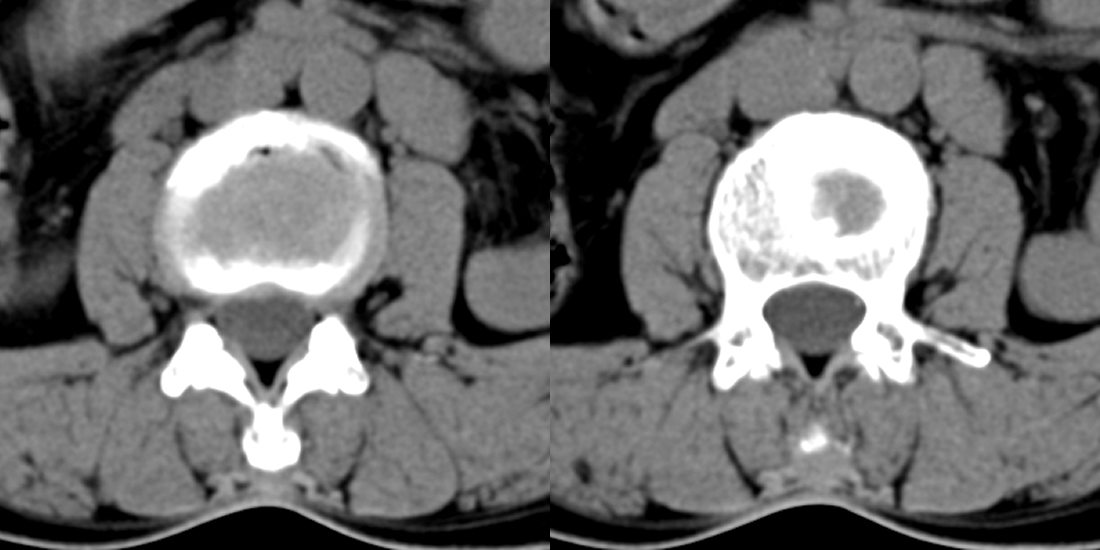

1)l3椎体上缘许莫氏结节。2)腰椎退行性改变。

l3椎体上缘许莫氏结节。腰椎退变。